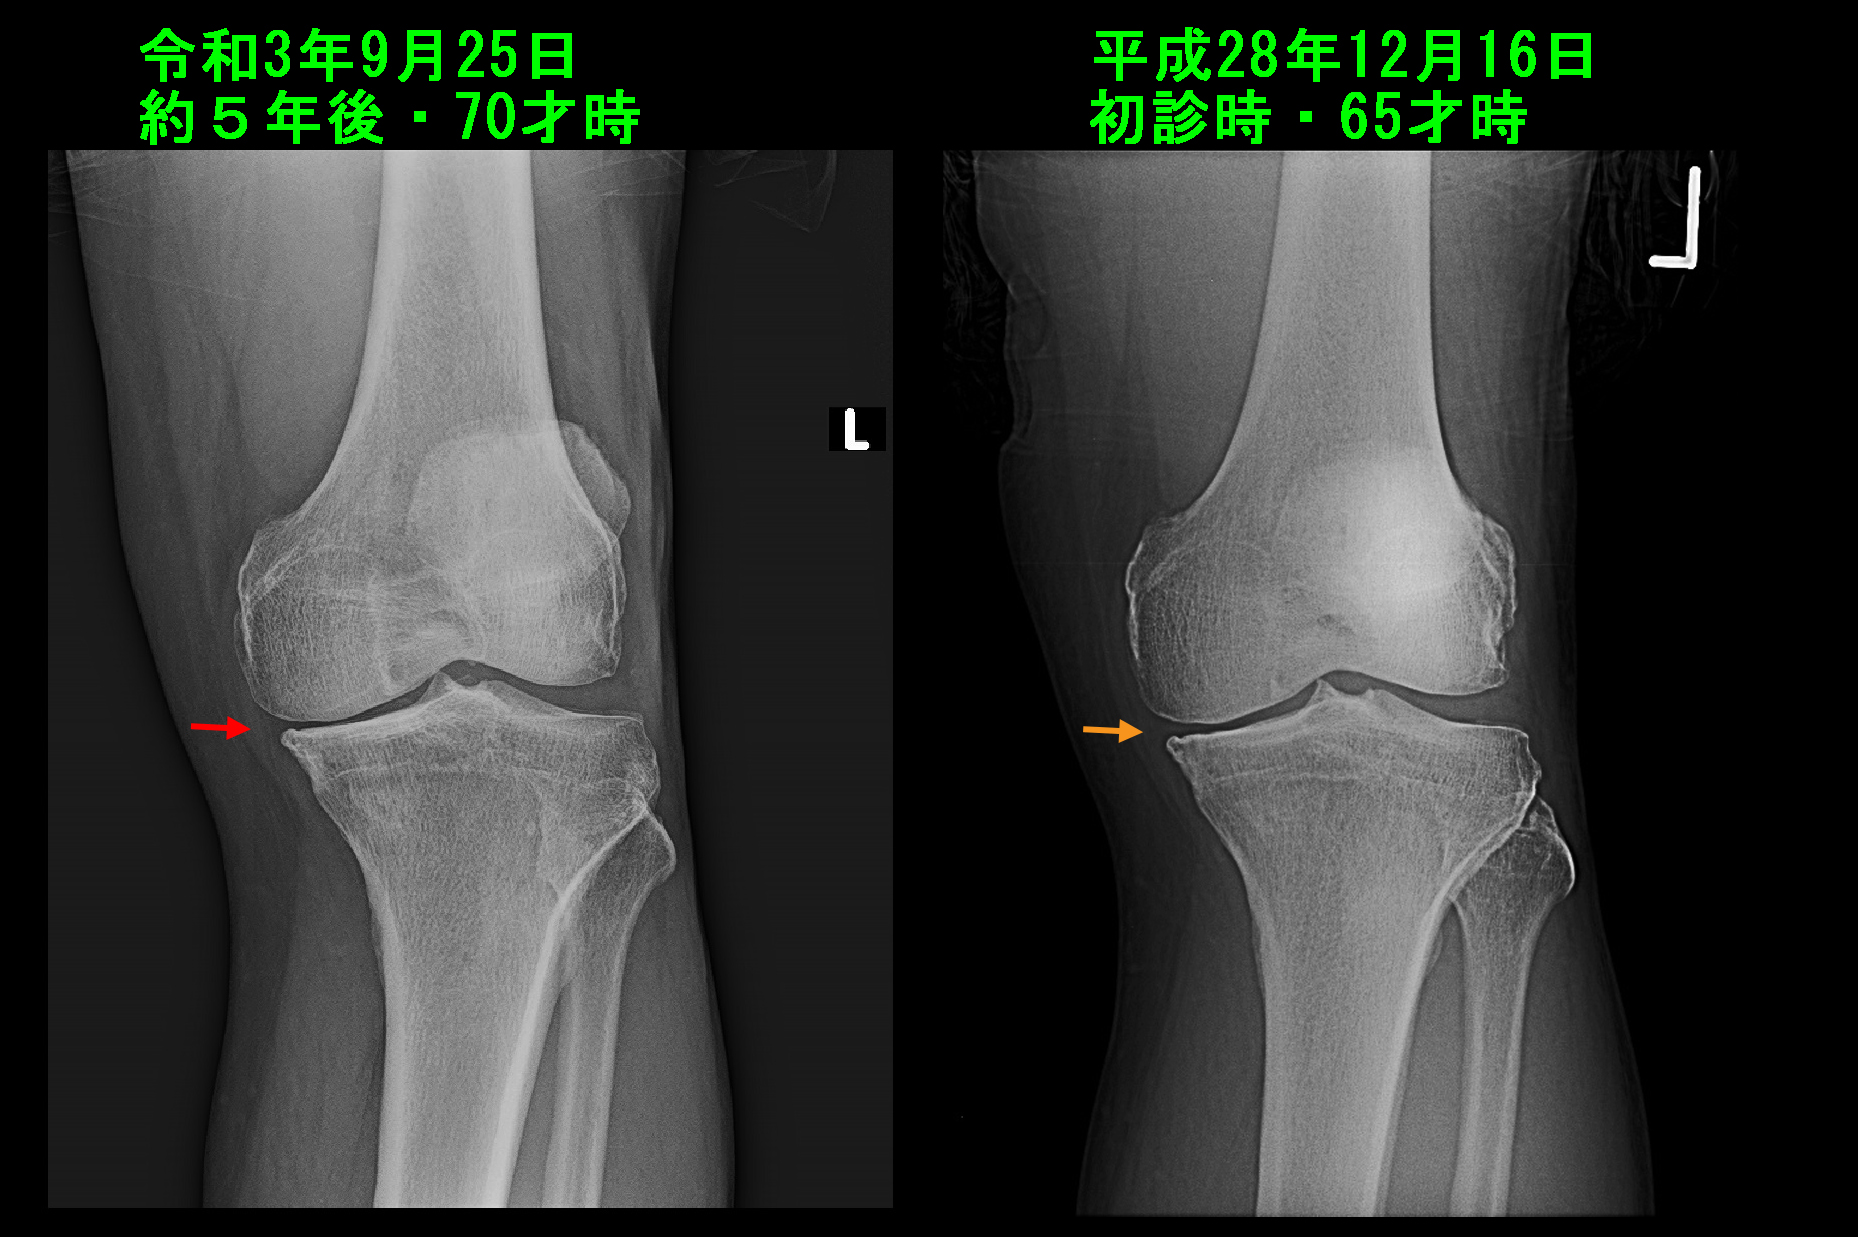

もう1人、ほぼ同じ期間変形性膝関節症の保存的治療を継続していた患者さんの左膝のレントゲン像を提示したいと思います。

70才の果樹と野菜を作っている農家の男性です。先の77才の女性の患者さんが手術を希望された翌日の令和3年9月25日に月1回の定期的な受診をされました。

70才男 Xp.jpg

この患者さんは5年前の平成28年12月16日に左膝痛で当院を受診され、中等度の左変形性膝症に対して投薬とともに月1回のヒアルロン酸製剤関節内注入療法を継続してきました。左膝の内側の関節裂隙は5年の経過で軽度狭くなっていますが(オレンジ矢印と赤矢印)、5年の経過で先の77才女性の患者さんのように関節裂隙が消失し、骨まで摩耗して崩れるというような印象は全くありません。投薬は痛みを軽減するための対症療法でしかなく、関節軟骨の摩耗の予防はヒアルロン酸製剤によっているわけですが、十分な治療効果が表れていると理解して良いと思われます。

ヒアルロン酸製剤関節内注入療法による関節軟骨の摩耗予防と服薬による痛みの軽減を図りながら、患者さんの膝の老化の進行が停止して、生活状態で過剰な負担が膝にかからなくなれば膝痛は一定軽減し、落ち着く可能性があります。

このページではヒアルロン酸製剤関節内注入療法という保存的治療により、膝の老化の進行を抑えられるということを説明していますが、そのような治療をしていれば必ず老化の進行を予防できるわけでもありません。70才の男性の症例でも、5年の経過で内側の関節裂隙は軽度狭くなっていました。ヒアルロン酸製剤の治療効果は出ていると評価していますが、老化の変形は幾分進行しているのです。